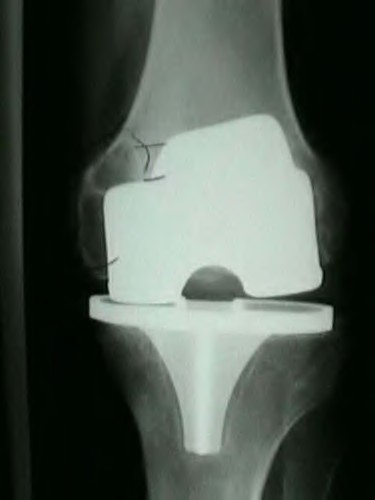

During a primary total knee arthroplasty (TKA), the surgeon evaluates the flexion and extension gaps. Utilizing spacer blocks, the surgeon notes that the extension gap is symmetric and perfectly balanced, but the flexion gap is excessively tight. Assuming an anterior referencing sizing guide was used, which of the following surgical adjustments is the most appropriate next step to balance the knee?

Options:

Correct Answer: Downsize the femoral component

Explanation:

When using an anterior referencing system, the anterior flange of all femoral components rests on the same cut surface. Downsizing the femoral component reduces its anteroposterior dimension by removing more bone from the posterior condyles. This specifically enlarges the flexion gap without altering the extension gap, thereby resolving an isolated tight flexion gap.